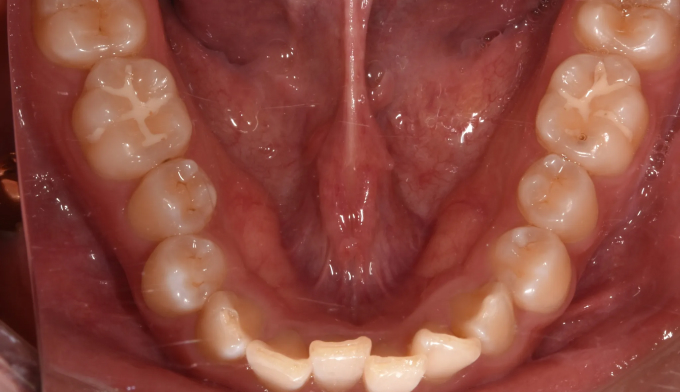

과개교합

과개교합은 앞니를 잇몸안으로 집어넣거나 반대로 어금니를 잇몸밖으로 빼내어 치료하는 방법이 있습니다.

환자의 안모 형태와 입술 두께등을 종합적으로 고려하여 치료방법을 결정합니다.

본 케이스에서는 치아 노출도를 고려하여 윗니를 위로, 아랫니를 아래로 함입하여 과개교합을 치료하였습니다.

교정기간은 총 10개월입니다.